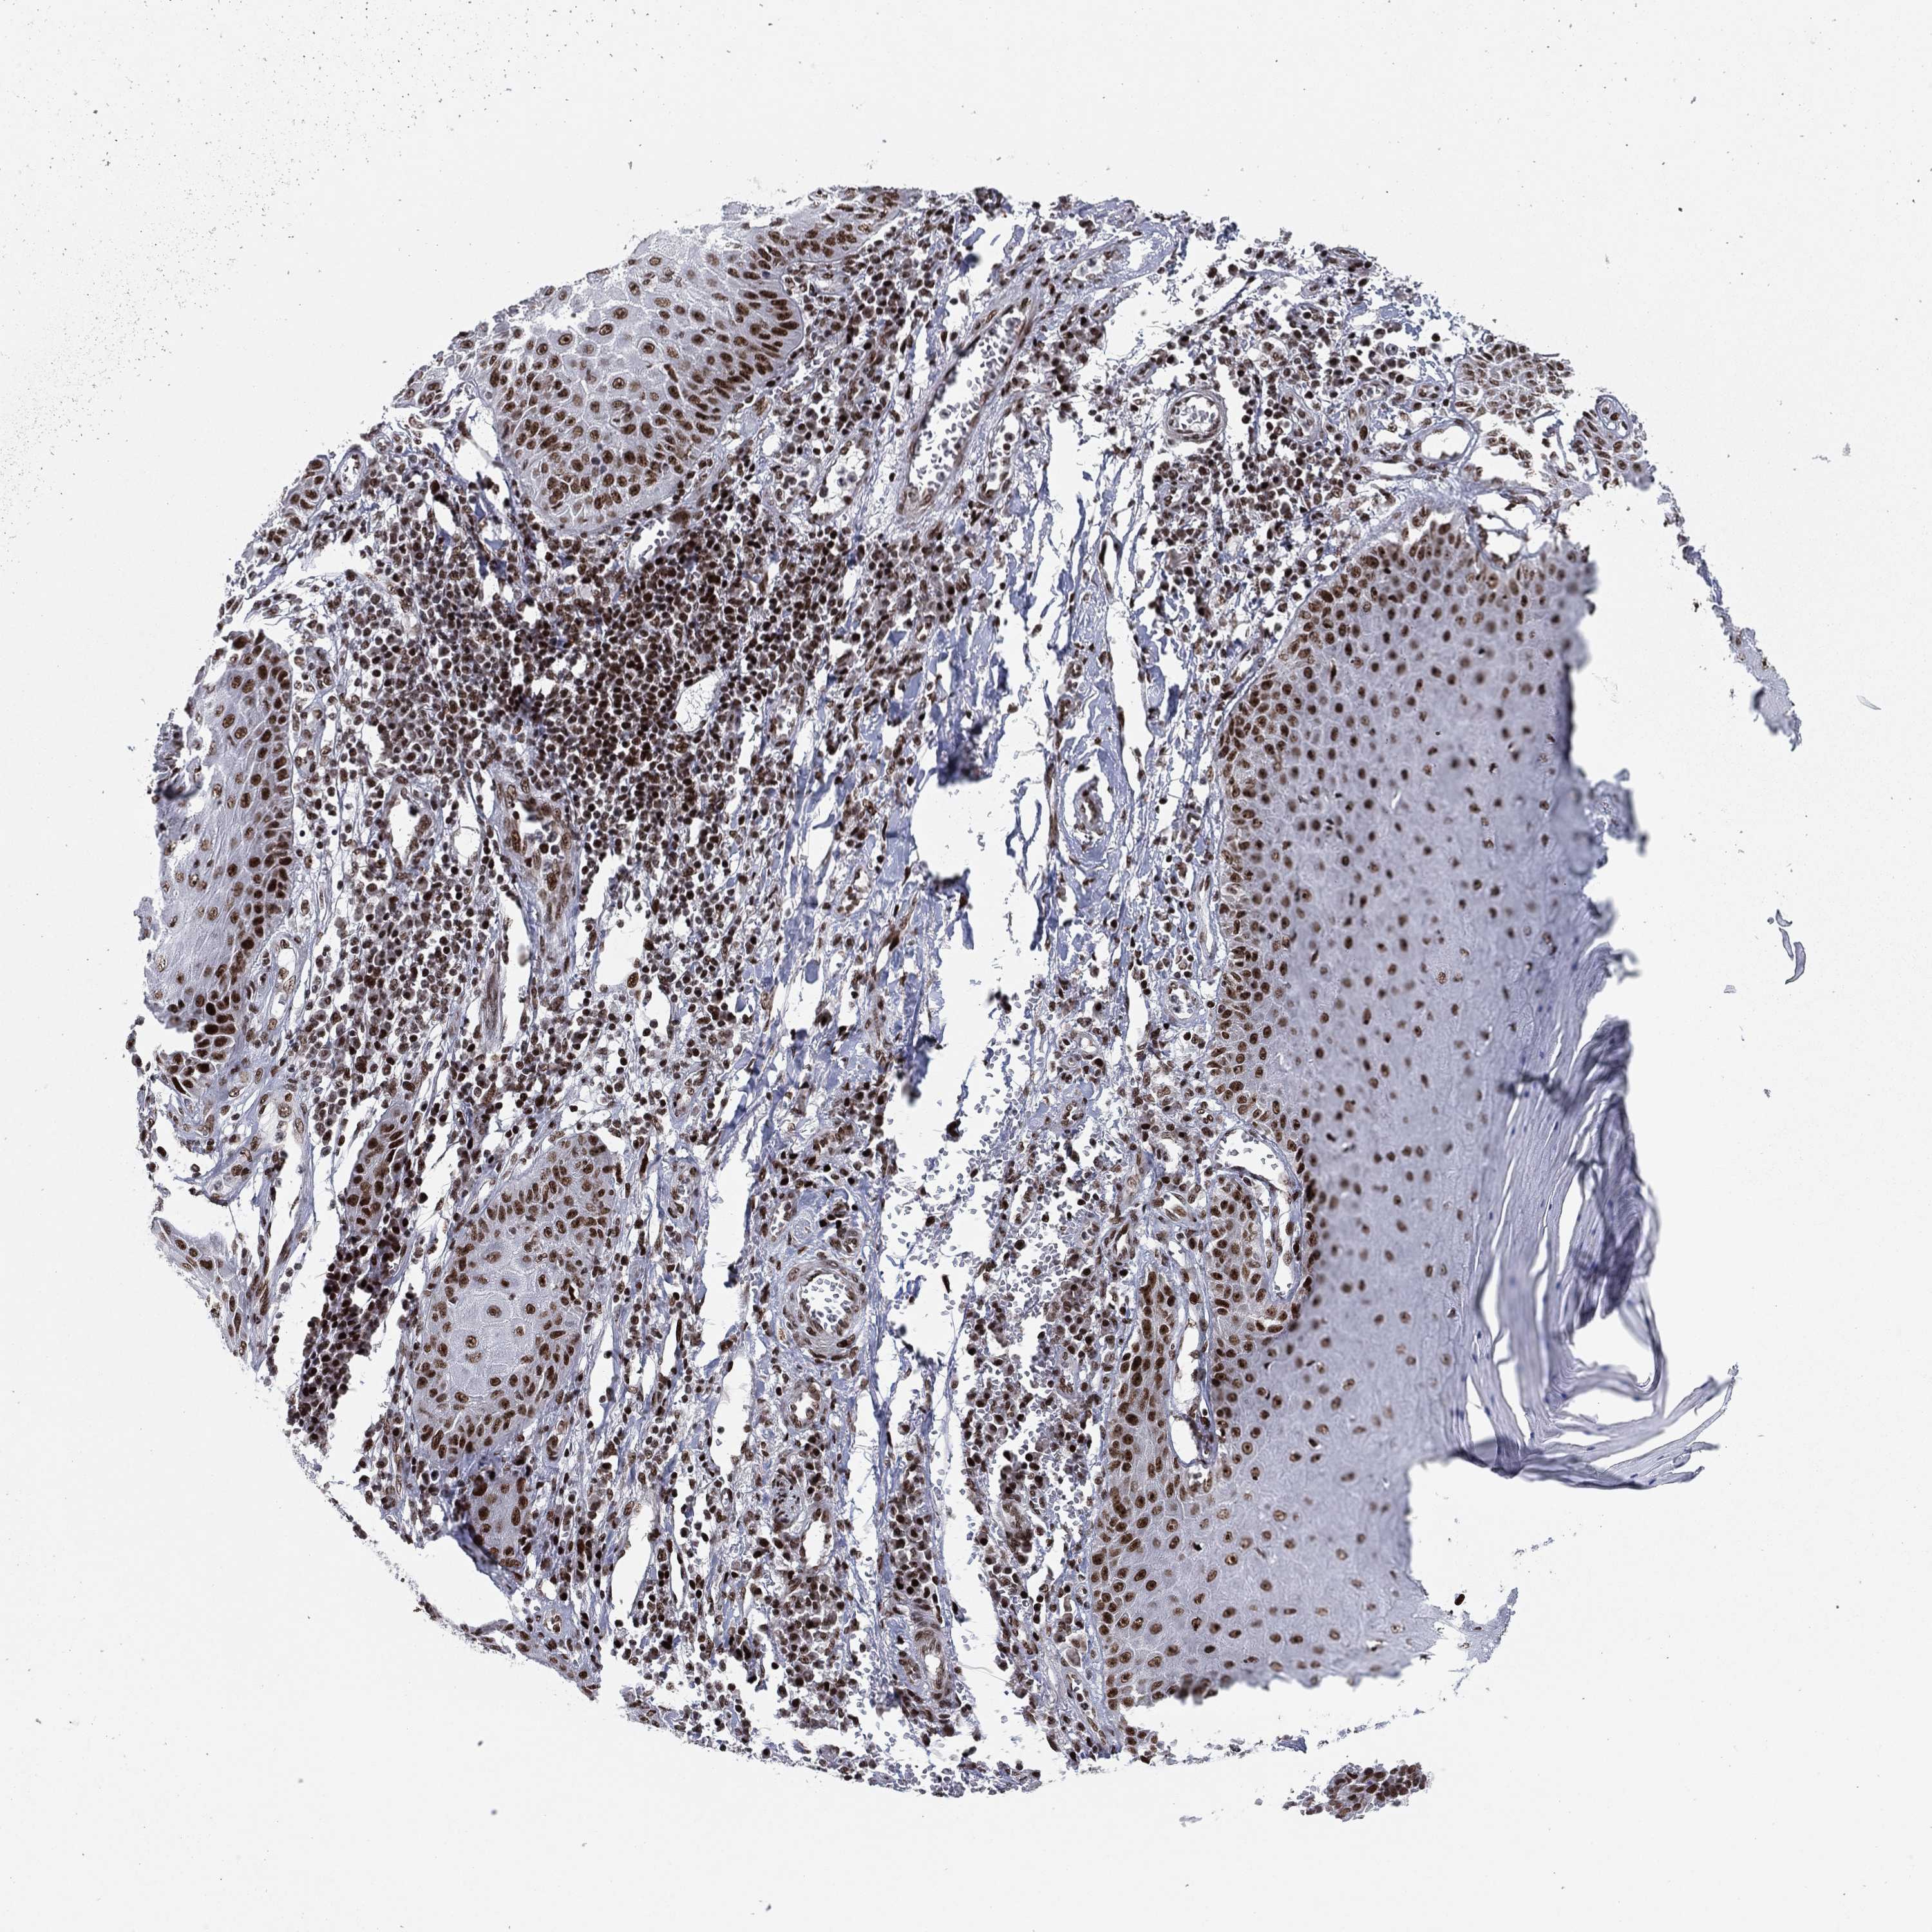

SKIN CANCER - Protein expressioni

A mouse-over function shows sample information and annotation data. Click on an image to view it in a full screen mode. Samples can be filtered based on level of antibody staining by selecting one or several of the following categories: high, medium, low and not detected. The assay and annotation is described here.

Antibody stainingi

Antibody staining in the annotated cell types in the current human tissue is reported as not detected, low, medium, or high, based on conventional immunohistochemistry profiling in selected tissues. This score is based on the combination of the staining intensity and fraction of stained cells.

Each image is clickable and will lead to virtual microscopy that enables deeper exploration of all samples and also displays staining intensity scores, fraction scores and subcellular localization as well as patient and tissue information for each sample.

Antibody CAB079947

Basal cell carcinoma

Papilloma, NOS